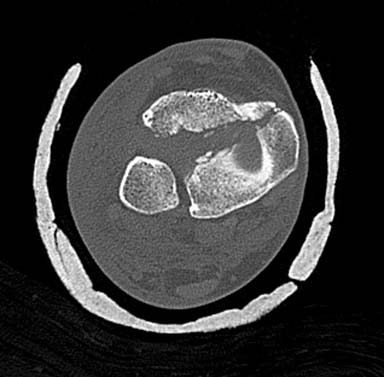

Первый случай, где перелом в результате падения с  небольшой высоты, где

мортиз рентген снимок показал отстутствие укорочения наружной

лодыжки и КТ срезы подсказали направления атаки. После такой фиксации

нет надобности в гипсовой повязке, брейс и через две недели движения в

суставе без нагрузки.